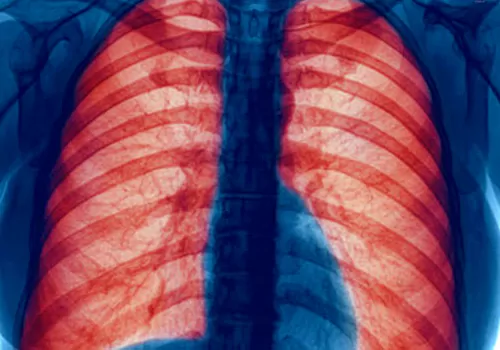

మీ ఊపిరి తిత్తులే మీ జీవితం ఇది నిజం...

మీరు ఆరోగ్యంగా ఉండాలంటే మీ ఊపిరితిత్తులు ఆరోగ్యంగా ఉండాలి ఇదే ప్రపంచ ఊపిరి తిత్తుల దినోత్చవం యొక్క నినాదం.ఆరోగ్య వంతమైన ఊపిరి తిత్తుల కోసం ప్రపంచ సి ఓ పి డి దినోత్చవం ప్రతిఏటా నవంబర్ మూడవ బుధవారం నిర్వహించడం ఆనవాయితీగా వస్తోంది. సి ఓ పి డి అంటే క్లినిక్ అపస్త్రక్టివ్ లంగ్ డిసీజ్ అని అంటారు మీ ఊపిరి తిత్తులే మీజీవితం ఈ నినాదమే మీరు దీర్ఘకాలం పాటు మీఊపిరి తిత్తులను ఆరోగ్యంగా ఉంచుతుంది . ప్రత్యక్షంగా ప్రపంచ వ్యాప్తంగా ౩91 మిలియన్ల ప్రజలు ప్రస్తుతం సి ఓ పి డి తో బాధ పడుతున్నారు.ప్రపంచంలో అత్యధిక మరణాలకు కారణం సి ఓ పి డి మూడో స్థానం లో ఉండని గణాంకాలు వెల్లడిస్తున్నాయి.భారత దేశం లో మరణాలకు ఊపిరితిత్తుల సమస్యలే రెండవ స్థానం ఆక్రమించింది అంటే ఊపిరితిత్తుల సమస్యలు ప్రణాలను ఏరకంగా కబళి స్తోందో అర్ధం చేసుకోవచ్చ్ఘు.దీనికి తోడు డిల్లి ముంబై వంటి నగరాలలో ఉన్న వాయు కాలుష్యం కూడా ఊపిరి తిత్తుల సమస్యలకు కారణంగా నిపుణులు పేర్కొన్నారు.సి ఓ పి డి పై ప్రజలకు అవగాహన కల్పించడం సి ఓ పి డి డే లక్ష్యం గా పేర్కొన్నారు. మీ ఊపిరి తిత్తులు బంగారం తో సమానం మీ ఊపిరి తిత్తులు ఆరోగ్యంగా ఉన్నంతకాలామే వ్యక్తి జీవిన్చాగాలడను ఒక్కసారి ఊపిరి తిత్తుల సమస్యలు వచ్చాయో ఊపిరి ఆగిపోవడం ఖాయం కాబట్టి మీ ఊపిరి తిత్తులు ఆరోగ్యంగా ఉండాలంటే మీ ఊపిరితిత్తులు ఏమి చేస్తాయి. ఊపిరితిత్తులకు సమస్యలు రావడానుకి కారణాలు తెలుసుకోవడం అవసరం.

యువర్ లంగ్స్ ఫర్ లైఫ్ మీ ఊపిరి తిత్తులు బలంగా ఆరోగ్యంగా ఉంటేనే జీవించడం సాధ్యం.మీఊపిరి తిత్తులలో మీ ఆరోగ్యం మీకు కనిపిస్తుంది మీరు ఊపిరి పీలుస్తున్నప్పుడుకష్టంగా ఉండడం లేదా అడ్డుపడడం అసమస్య రిజంతా కొనసాగడం కష్టం గా ఉండడం కనిపిస్తుంది.ఈ సమస్యలకు ముఖ్యంగా గ్రామీణ ప్రాంతాలాలో దోమల నివారణకు కోయిల్స్ రేపలేన్ట్స్ వాడడం పెరుగుతున్న వాయు కాలుష్యం ప్రధానంగా చెప్పవచ్చు.సి ఓ పి డి కి కారణం ముఖ్యంగా పొగతాగడం అది మీ ఊపిరి తిత్తుల నాళాలలో పేరుకు పోయి ఊపిరి తిత్తలు చెడిపోడానికి ఆస్కారం ఉంటుంది. కొన్ని సందర్భాలలో మీఊపిరి తిత్తులు చేడి పోడానికి కారణం కాదాని దీర్ఘకాలంగా అక్కడా సమస్య ఉందని గ్రహించాలి ఊపిరి తిత్తులు కుంచించుకు పోవడం వల్లా ఊపిరి తీసుకోవడం ఇబ్బందిగా మారడం. చెస్ట్ ఇన్ఫెక్షన్ దగ్గు తోపాటు కఫం వంటి లక్షణాలు గమనుంచాలని అంటున్నారు నిపుణులు. సి ఓ పి డి తీవ్రత ను గుర్తిస్తే ప్రాణాలు కపాదవచ్చని లేదంటే ప్రాణాలు పోతాయని నిపుణులు హెచ్చరిస్తున్నారు. ఊపిరి తిత్తుల క్యాన్సర్ వచ్చే అవకాసం ఉందని నిపుణులు హెచ్చరిస్తున్నారు.